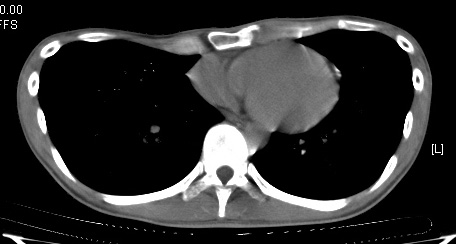

約9點左右,朱醫師走出來,並且拿剛用平板拍的手術後胸部照片給我們看,這時才覺得安心不少,再加上朱醫師說手術很成功順利,手術的這一關算是度過了..